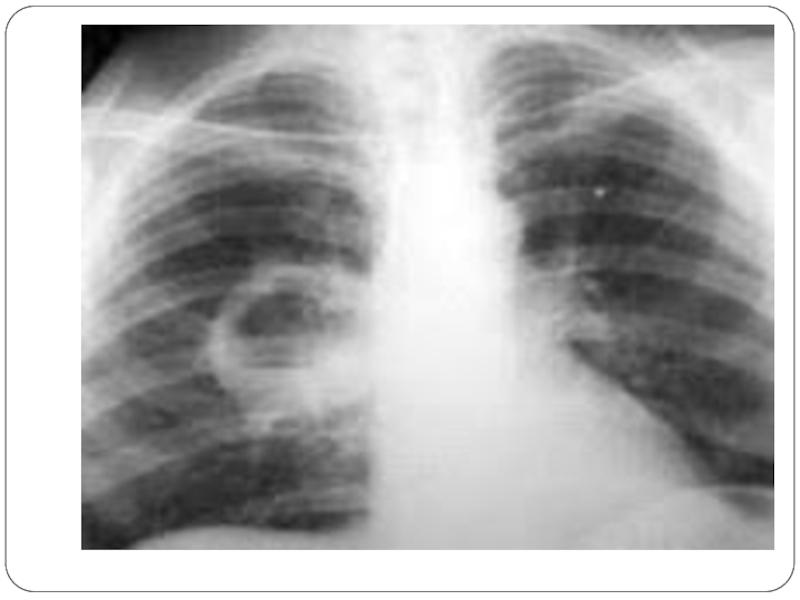

ауру сезімі, ентігу, тахикардия пайда болады. Аталған белгілердің айқындалу дәрежесі үрдістің таралуына және ағзаның қорғаныс функцияларының жағдайына байланысты. Аускультацияда зақымданған аймақта қатаң тыныс анықталады. Кей жағдайда крепитацияланған сырылдар және плевраның үйкеліс шуын естуге болады, ал зақымданған аймақта перкуторлы дыбыс қысқарады. Рентгенограммада және компьютерлі томограммада осы кезеңде зақымданған өкпеде гомогенді қараю, қабыну инфильтраты анықталады.

Слайд 16Рентгенологиялық зерттеу кезінде қуыс қабырғасының қалындауын анықтауға болады. 2 ай

өткеннен кейін абсцесс сұйықтық деңгейі бар дөңгелек қуыс ретінде көрінеді,

сонымен қатар өкпе инфильтрациясы байқалады

Рентгенологиялық зерттеу кезінде қуыс қабырғасының қалындауын анықтауға болады. 2 ай өткеннен кейін абсцесс сұйықтық деңгейі бар дөңгелек